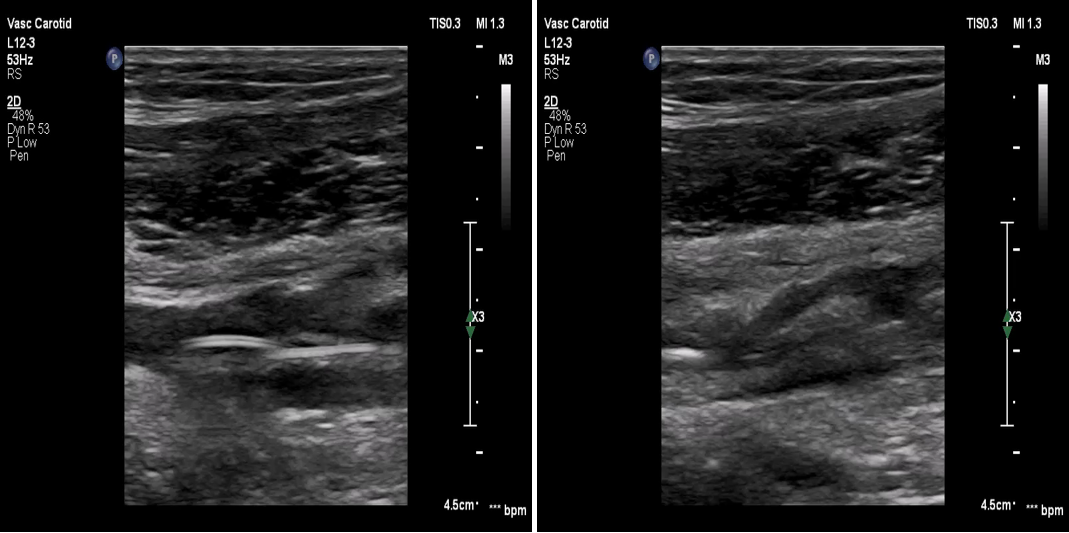

术前检查:右髂动脉血栓

图:术前CT

图:术前超声

手术操作:系统溶栓治疗3天,症状未缓解,考虑其血栓时间较长,超声引导下行右髂动脉覆膜支架置入术